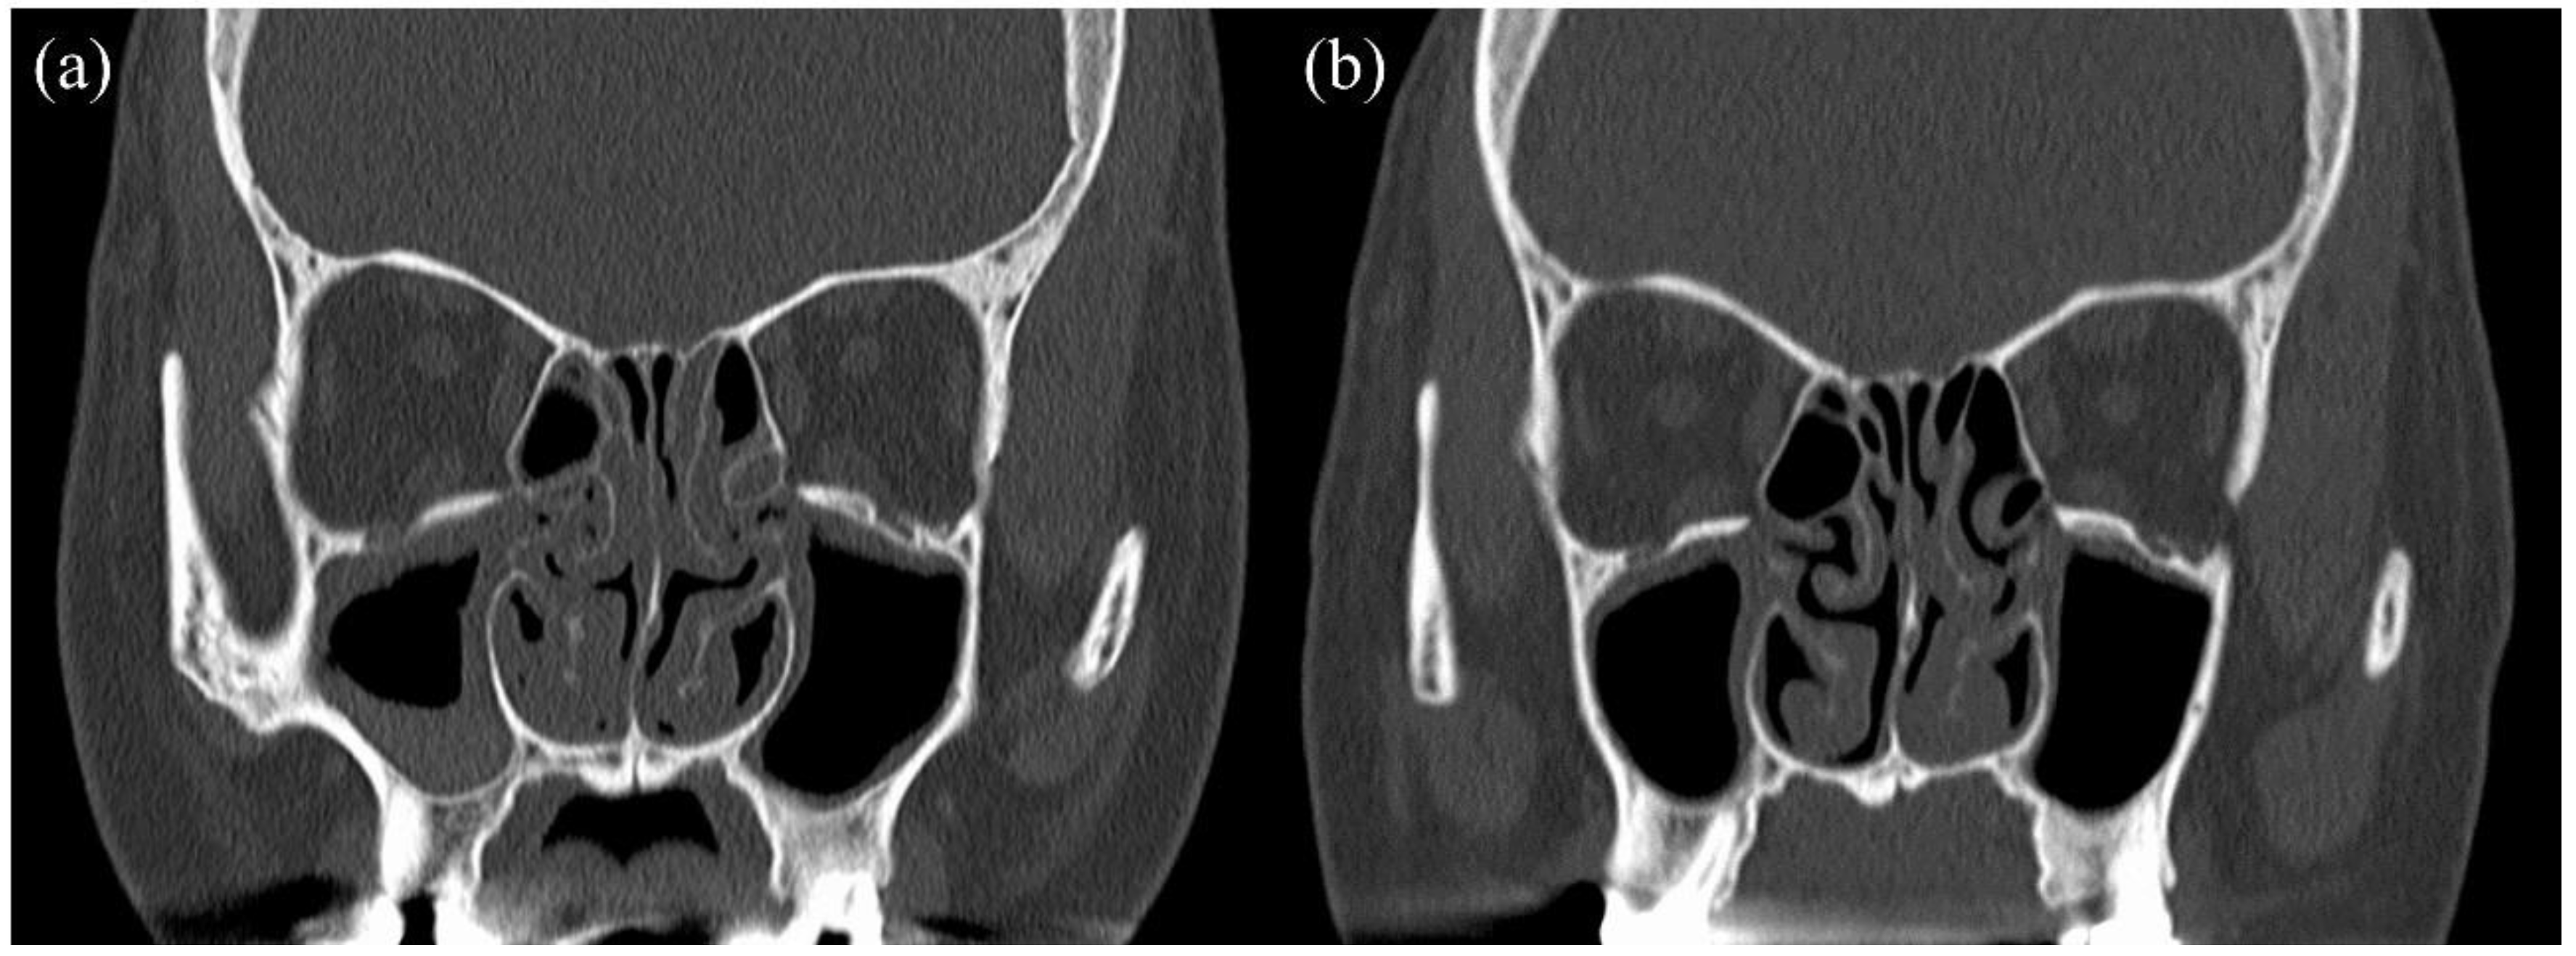

Herein, we describe the case of a 41-year-old woman who was referred for treatment of severe asthma. She was a non-smoker. She had been receiving one puff of vilanterol trifenatate 25 μg and fluticasone furoate 200 μg once daily and two puffs of tiotropium bromide hydrate 2.5 μg once daily. She was also taking montelukast sodium (10 mg daily). As stage lighting staff, she had to miss work once a month due to asthma exacerbation, and she used oral corticosteroids (OCS) for each asthma exacerbation. She reported the loss of her sense of smell, dizziness, and otorrhea, as well as complicated ECRS and EOM. Her EOM was diagnosed when she was 33 years old. She underwent multiple bilateral myringotomy and tympanostomy tubes due to severe EOM. The clinical findings at the first visit were as follows: % predicted FEV1, 37.7%; FeNO, 26 ppb; blood eosinophil count, 2441 cells/μL; total IgE level, 657 IU/mL. Her specific IgE levels for vernal grass, dactylis, Japanese cedar, cypress, and Aspergillus were positive. The ACQ score at that time was 4.4 points. The patient’s treatment course is shown in Figure 1. First, mepolizumab, which is a monoclonal anti-IL-5 antibody, was initiated for severe eosinophil asthma. Three months later, she was no longer absent and her ACQ improved to 2.8 points, but the need for OCS due to frequent exacerbations remained. Thus, we considered that mepolizumab had insufficient therapeutic efficacy and started with omalizumab, an anti-IgE antibody. Two months later, the asthma exacerbation decreased, OCS was no longer necessary, and the % predicted FEV1 improved to 85.2%. However, the loss of her sense of smell, dizziness, and otorrhea caused by ECRS and EOM persisted, and she still had trouble working. Thereafter, these symptoms did not improve, and the blood eosinophil count increased. Nineteen months after the initiation of omalizumab, we switched to benralizumab, which is an anti-IL-5 receptor alpha antibody. During the third month after the initiation of benralizumab, her blood eosinophil counts decreased to 0 cells/μL, and her ACQ improved to 0.2 points. Although we continued treatment with benralizumab for approximately 25 months, her otorrhea, dizziness, and loss of sense of smell worsened. Especially for EOM, there was no improvement in her hearing level, and the therapeutic efficacy was poor. We hypothesized that sequential biologic therapy with benralizumab as anti-IL-5 therapy and dupilumab, which inhibits IL-4 and IL-13 signaling, would have a significant effect in this patient based on the following reasons: (i) the inadequate response to treatment with mepolizumab and omalizumab, (ii) the effects of treatment of asthma with benralizumab, (iii) prolonged high FeNO levels, and (iv) promising data on therapeutic response to dupilumab for ECRS. Therefore, we initiated sequential biotherapy, which comprised a cycle of dupilumab administration four times every 2 weeks for 2 months after a single administration of benralizumab per month for 2 months. Sequential biotherapy was initiated not only to maintain asthma control but also to improve the sense of smell and otorrhea and suppress the progression of ECRS and EOM. Subsequently, asthma control remained well maintained, and the sense of smell, dizziness, hearing level, and otorrhea improved. Moreover, she no longer had any problems with work. Figure 2 shows a sinus CT before and after sequential biotherapy. After sequential biotherapy for 7 months, improvements in sinus shadowing were observed. The ACQ at that time was 0 points, and % predicted FEV1 was 89.9%. She is still undergoing sequential biotherapy.

Figure 2.

Sinus CT before and after sequential biotherapy: (a) before sequential biotherapy, (b) after sequential biotherapy for 7 months.